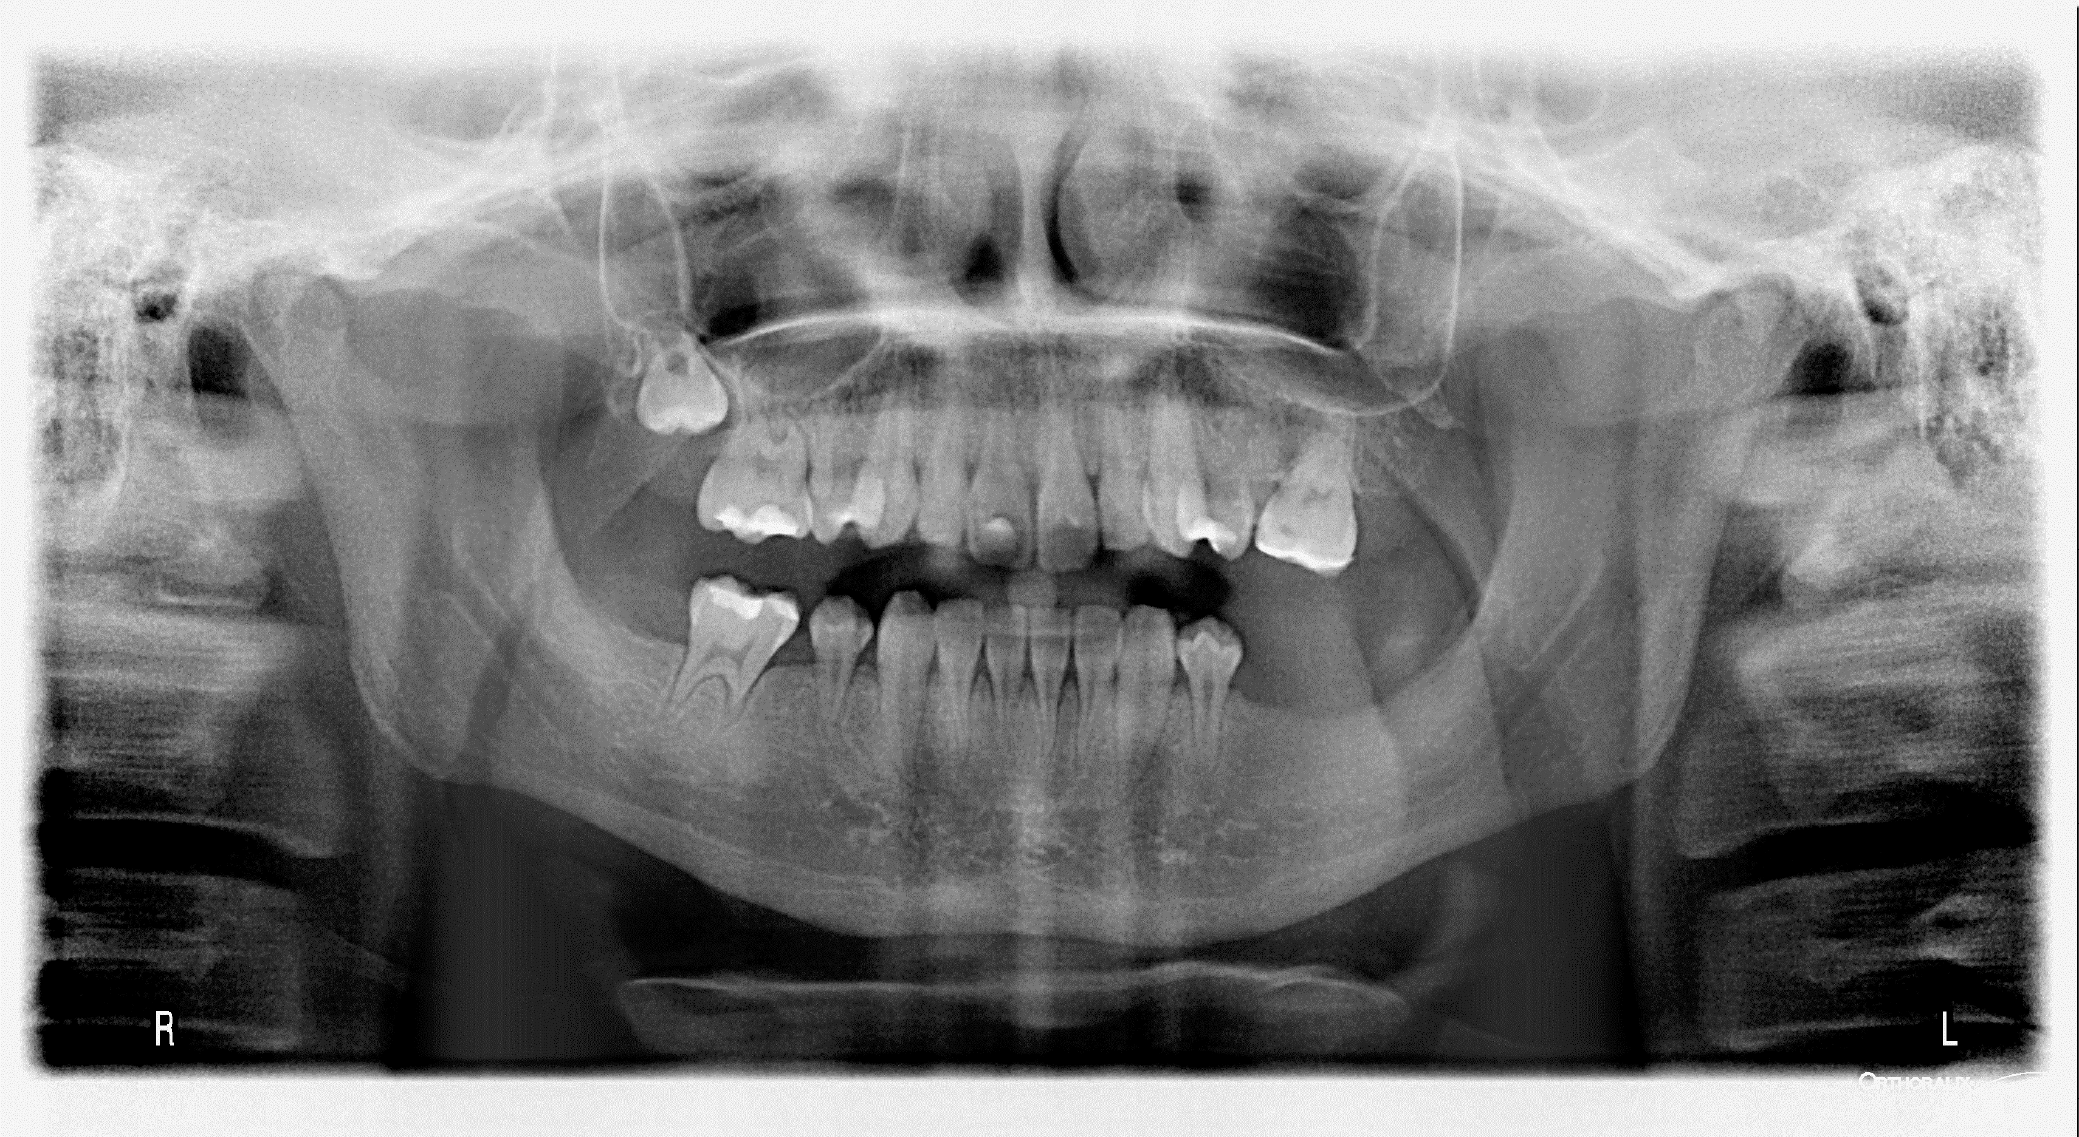

Figure 4 presents an exemplatory panoramic radiograph of a 15-year-old male patient diagnosed with neuroblastoma at the age of 3. The patient underwent a 21-month treatment regimen consisting of combination therapy, which included high-dose and conventional CT, bone marrow transplantation and RTX. The patient suffers from hypodontia, short roots of teeth and microdontia.